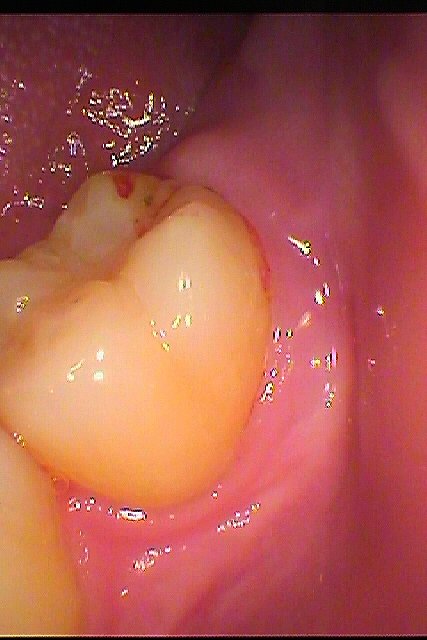

全く親知らずが見えません

歯茎が腫れているようです

親不知が見えてきました